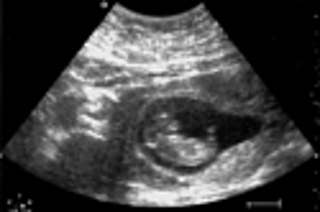

Texas Sonogram Abortion Bill Passed

Texas lawmakers have passed legislation requiring doctors to perform a sonogram at least 24 hours before conducting an abortion...Proponents say the law is necessary to make sure women understand what an abortion entails (WTF?!). Opponents say it would interfere in the doctor-patient relationship... a statement issued by NARAL Pro-Choice Texas, a non-profit state-wide organization, on the legislation: "Patrick consistently fails to publicly mention the hardship that the 24-waiting period between the sonogram and abortion will cause for those who live in the 93% of Texas counties that don't have an abortion provider. Indeed, this bill is designed to shame women, as if we are daft creatures unable to make personal, private medical decisions without the paternalistic oversight of legislators." ****My Body=My Right To Choose, Assholes****